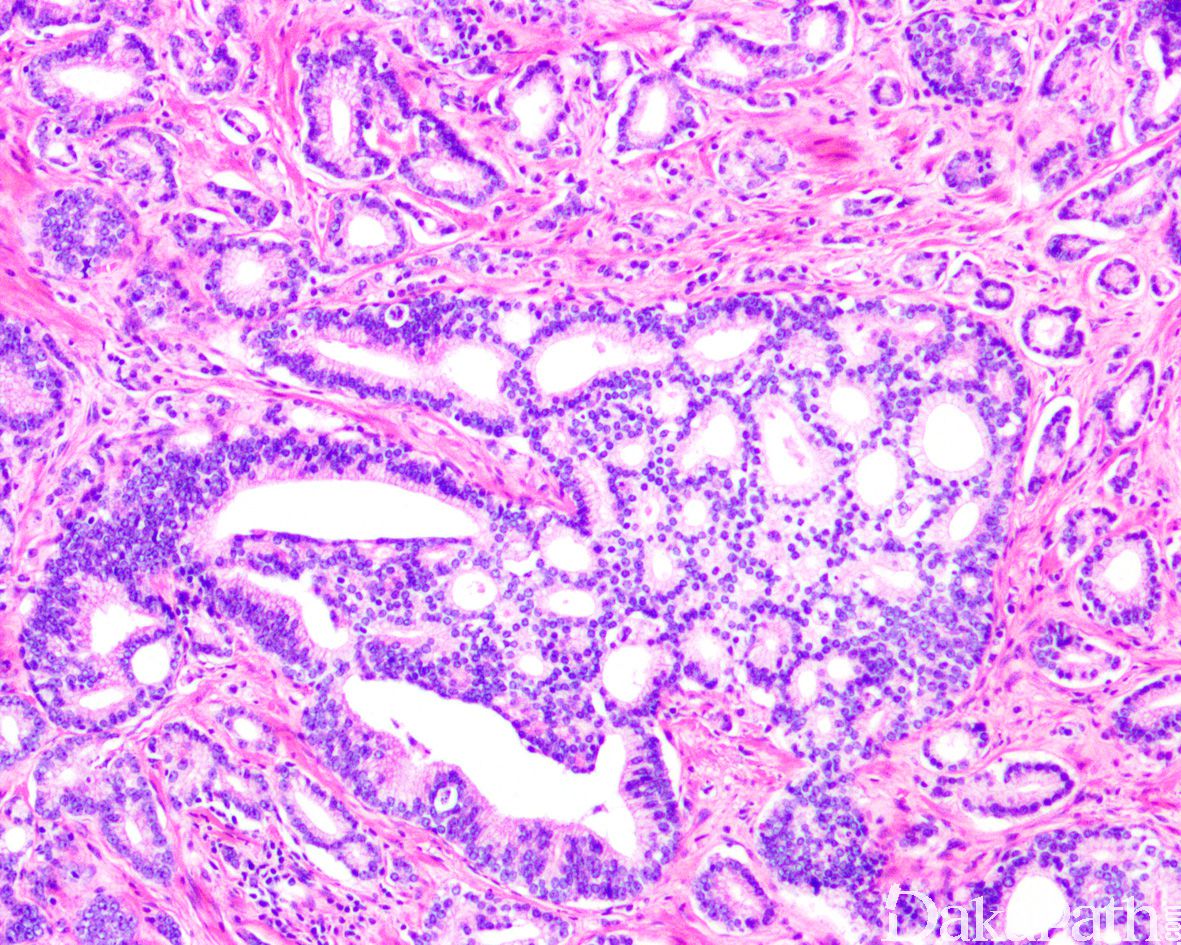

IDC-P 的组织学特征为癌细胞在前列腺固有腺体内膨胀性增生并至少局灶保存有基底细胞。

在 IDC-P 的前列腺根治切除标本中,一般至少存在 6 个以上的 IDC-P 腺体,肿瘤腺体的直径一般为邻近正常的外周带腺体大小的 2 倍或以上,常显示不规则的分枝状轮廓。IDC-P 存在几种组织学生长方式,(1)疏松筛状结构,2 个细胞厚度的细胞条带相互交错,填充腔面,在周围形成花边状的空腔,无支持性间质;(2)微乳头状结构,增生的细胞簇无明显的纤维血管轴心;(3)致密筛状结构,小而圆的凿除状规则腔隙不超过腺腔面积的 50%;(4)实性膨胀性结构。被覆上皮立方状或矮柱状,具有明显的细胞异型性和核的多形性,有时核的大小是邻近良性前列腺细胞核大小的 6 倍以上,常见粉刺样坏死(图 1-4)。

诊断 IDC-P 的形态学特征,包括 5 个主要和 3 个次要标准。前 4 个主要标准总是存在于 IDC-P 中,包括:(1)直径超过正常外周腺体 2 倍以上的大腺体,(2)存在基底细胞,可通过基底细胞标志物予以识别,(3)细胞学上恶性的肿瘤细胞,以及(4)膨胀性的细胞增殖在腺腔内生长。诊断 IDC-P 的第 5 个主要标准是中央粉刺样坏死,但并不总是存在。次要标准包括腺体具有(1)呈直角的分支或(2)平滑的,圆形的轮廓;以及(3)两群细胞,位于外层的高柱状细胞,多形性,核分裂象高,对前列腺特异性抗原(PSA)染色较差,位于中央的立方形细胞,形态单一,核分裂像不活跃,具有多量富含 PSA 的胞质,偶尔可能存在细胞外黏液。

前列腺穿刺活检标本中 IDC-P 的诊断标准,诊断 IDC-P 需要存在(1)实性或密集的筛状结构,其中凿除状规则的空腔不超过腺腔面积的 50%;或(2)明显的核异型性,肿瘤细胞核的大小至少超过邻近的良性腺体细胞核的 6 倍;或(3)非局灶性的粉刺样坏死。当鉴别诊断为 HGPIN 和 IDC-P 时,病变如果没有满足 IDC-P 的诊断标准但不典型性较 HPGIN 显著,则诊断为非典型导管内上皮增生(atypical intraductal proliferations)。